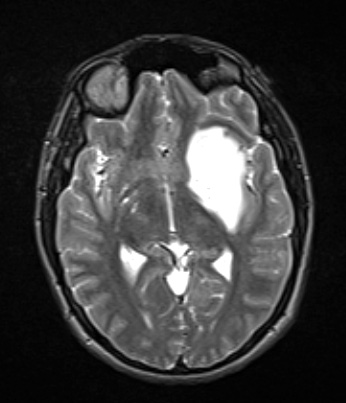

Case 7 History ---- The patient is a 24-year-old man with a history of diffuse glioma with IDH-R132C mutation. Cytogenetic abnormalities include polysomy of chromosome 1, 19 and 7 without EGFR gene amplification or 1p19q co-deletion. Operative procedure: Left insular/temporal MRI-guided Monteris laser ablation. ---- Prior to any surgery the following images were obtained. ---- 7A1This T2-weighted contrast applied image shows a large hyperintense mass involving the insular and temporal cortices.